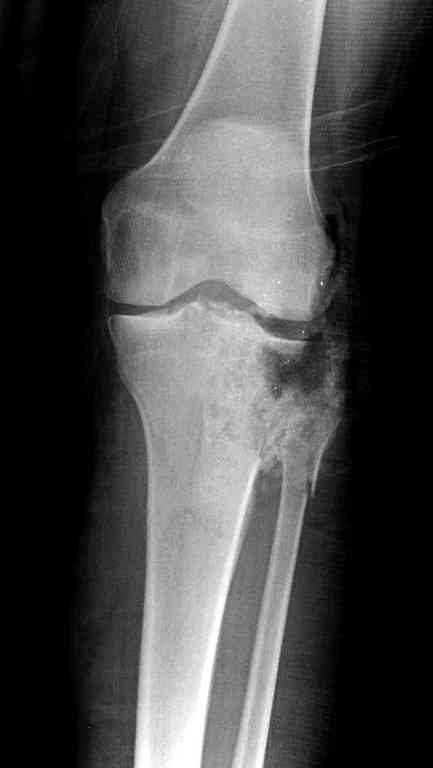

Поступила к нам пациентка 19 лет с диагнозом "Состояние после открытого многооскольчатого перелома дистального метаэпифиза правого бедра, проксимального метаэпифиза большеберцовой кости". Травма в июне 2010 года в Индии. ДТП.

Тамошние доктора выполнили ПХО с удалением фрагментов латерального мыщелка бедра. Наложен АВФ. По возвращению в Украину через 1,5 месяца АВФ демонтирован. И так как смещение фрагментов бедра не устранено, было принято решение после заживление ран от стержней выполнить МОС. Не сколько для четкой анатомической репозиции сколько для подготовки к установке эндопротеза в будущем. Что и было выполнено 10 августа. Интраоперационная картина следующая. Дефицит практически всего латерального мыщелка бедра. Была выполнена попытка закрепить то что осталось от мыщелка, но он развалился на фрагменты. ВЫполнен ситуационный синтез спицами. Дефект заполнили бикортикальным трансплантатом из крыла подвздошной кости, МОС страйкеровским фиксатором. В послеоперационном периоде к 10 дню начались боли, гипертермия. Повышение СОЭ, лейкоцитоз. Посев крови транзиторная бактериемия золотистого стаф. Взяли в операционную. Выполнили дренирование сустава и области п\о раны. Получили гематому фактически с гноем. Температура нормализовалась. Назначили ванкомицин по 1000 мг 2 раза в день.который принимает с 28 августа по сей день. Температура нормальная, СОЭ на убыль. Посевы отделяемого стафилококк 2 ст активности. Но отделяемое по дренажам продолжает идти в достаточном количестве. Взял посев, сеется стаф. 3 ст активноси. К ванкомицину, понятно, слабочувствителен. Что в этой ситуации посоветуете?

Хотелось увидеть снимки и что за "страйкеровский фиксатор" их много.И для дальнейшего эндопротезирования нужна анатомическая репозиция.Как связочный аппарат сустава?

На вашем снимке из-за ротации трудно угадать положение пластины, и желательно сделать снимок с захватом верхнего участка бедра.

Одинокий кортикальный шуруп не удержит тибиальный бугор, сустав тибиал плато оставлен без репозиции и фиксации.